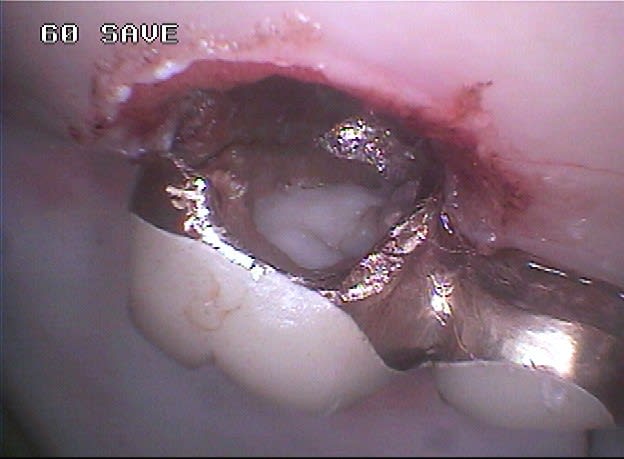

Ceci est un exemple de traitement de poches par photo-ablation en une seule séance en mode continu sans contact, cette technique diffère des traitements par lasers fibrés.

Après sondage et traitement médical, la gencive non attachée est volatilisée avec stérilisation et hémostase immédiate. La cicatrisation est rapide et la ré-attache se réalise en quelques jours, laissant dégagés les espaces biologiques afin de permettre un entretien aisé par le patient, la texture de la gencive prenant un aspect en peau d'orange et reformant progressivement un feston.

Marc, évidemment qu'il s'agit de gingivectomie, je dirais même plutôt gingivoplastie, la gencive est sculptée par le laser plus fidèlement qu'avec un bistouri ou une fraise car il suit exactement le trajet et la profondeur de chaque poche sans sectionner à l'emporte pièce.

J'ai rajouté les photos vestibulaires sur mon premier post, les poches étant un peu moins profondes qu'en palatin.

La différence ne s’arrête pas seulement là, car comme te l'a très bien expliqué Emma, le laser représente bien plus qu'un simple instrument de coupe ou de nettoyage, aucun bistouri ni aucune curette n'est capable de stériliser, d'assurer l'hémostase immédiate, d'activer la cicatrisation ou encore de pratiquer une suture avec un confort pour le patient nettement amélioré. Tu pourrais à la rigueur le comparer à un bistouri électrique mais celui-ci n'a qu'un effet de surface limité.